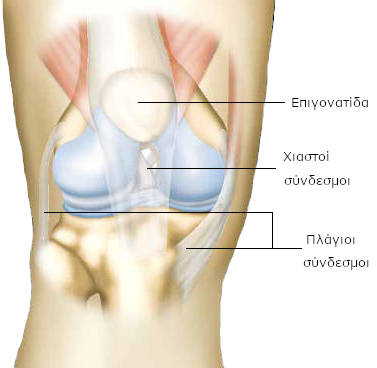

Το γόνατο ενώνει το μηρό με την κνήμη. Το μηριαίο είναι το οστό του μηρού. Η κνήμη είναι το οστό που βρίσκεται κάτω από το γόνατο, στο μπροστινό μέρος του σκέλους, ενώ η περόνη βρίσκεται προς τα έξω και πίσω. Η άρθρωση του γόνατος αποτελείται από το κατώτερο τμήμα του μηριαίου οστού (μηριαίος κόνδυλος) και το ανώτερο τμήμα της κνήμης (κνημιαία γλήνη).

Η επιγονατίδα αποτελεί το τρίτο οστό της άρθρωσης του γόνατος. Συγκρατείται από το μυ του μηρού (τετρακέφαλο μυ) και βρίσκεται στο πρόσθιο τμήμα του γόνατος.

Το γόνατο στηρίζεται πλευρικά με τους έσω και έξω πλάγιους συνδέσμους, ενώ σταθεροποιείται με τους χιαστούς συνδέσμους, οι οποίοι, όπως δηλώνει και το όνομά τους, σχηματίζουν ένα Χ στην άρθρωση.

Ο πρόσθιος χιαστός σύνδεσμος εμποδίζει την πρόσθια μετατόπιση της κνήμης και ο οπίσθιος χιαστός σύνδεσμος την οπίσθια.